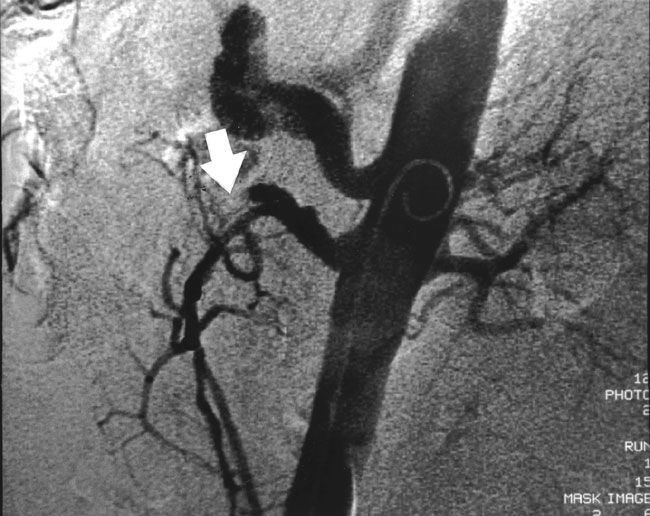

ArteriografíaGold-Standar